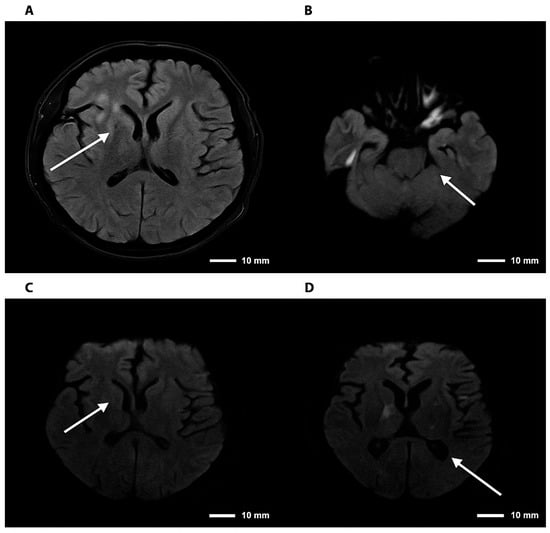

Initial laboratory studies revealed a blood glucose level of 78 mg/dL, C-reactive pro-tein of 1.7 mg/L, sodium of 128 mmol/L, and hyperkalemia of 5.4 mmol/L, with normal renal and hepatic function. Glycated hemoglobin was 5.3%. Given the patient’s immuno-suppression and rapid neurological progression, advanced neuroimaging was performed. Brain MR angiography demonstrated mild segmental stenosis in the middle and anterior cerebral arteries without significant occlusions; complete cerebral angiography was nor-mal. Brain MRI revealed focal hyper intense lesions in the right thalamus (10 × 6 mm2) and Globus pallidus, suggestive of infectious or inflammatory etiology (Figure 2) and (Figure 3).

Figure 3.

Brain magnetic resonance imaging—FLAIR and DWI sequences in cryptococcal meningoencephalitis. Note. Brain magnetic resonance imaging. (A) Axial FLAIR sequence showing hyperintensity in the right basal ganglia. (B) DWI sequence demonstrating diffusion restriction in the right thalamic region. (C,D) Axial DWI images confirming foci of restriction in the right basal ganglia and thalamus, consistent with an infectious/inflammatory process. The arrows indicate lesions consistent with cryptococcomas, involving the supra- and infratentorial parenchyma to varying degrees.